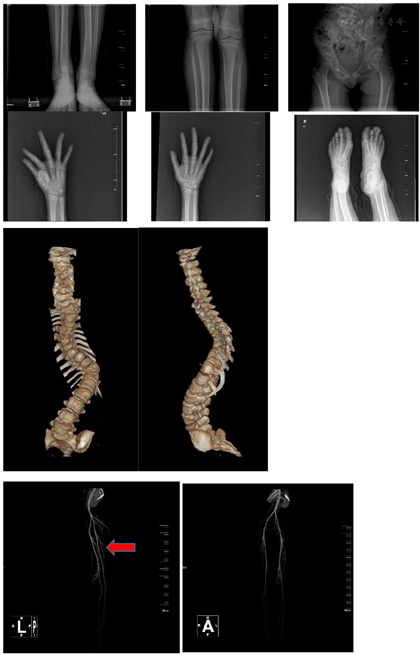

影像学检查:立位全脊柱正侧位片显示脊柱侧弯;双下肢X线显示右下肢短缩2 cm,左股骨头形态欠佳;头部CT平扫示左侧眼眶及额骨局部骨质膨大;双手手正斜位片示右手第3、4中指节较对侧膨大;双足正位片示右跟骨低密度影,右足第3近节趾骨远端、左足第2近节趾骨远端骨性突起,右足第3趾骨远端软组织肿胀;双下肢血管造影示左侧股动脉下端多发迂曲血管影,左侧髌骨上方肿块邻近髌骨骨皮质破坏,右下肢浅静脉曲张,大隐静脉多发分支与深部血管交通。体格检查:右足底4 cm×4 cm不规则脑回状结缔组织痣。基因检测:该患者受累组织全外显子组测序示受检者AKT1 c.49G>A突变。此突变为体细胞突变,根据以往的报道,该位点突变可能是本病的病因。

立位全脊柱X线片示脊柱侧弯,胸腰弯cobb角为96°(图4)。全脊柱CT+三维重建示脊柱侧凸、后凸畸形严重,部分腰椎发育不良。心电图、心脏彩超均未见异常。双手手正斜位片示右手第3、4中指节较对侧膨大。双足正位片示右跟骨低密度影右足第3近节趾骨远端、左足第2近节趾骨远端骨性突起。右足第3趾骨远端软组织肿胀(图1)。双下肢血管造影示左侧股动脉下端多发迂曲血管影(图2),左侧髌骨上方肿块邻近髌骨骨皮质破坏,右下肢浅静脉曲张,大隐静脉多发分支与深部血管交通。血常规:中性粒细胞百分率33.8%,淋巴细胞百分率52.7%,单核细胞百分率11.8%,中性粒细胞计数1.6×109/L。生化:碱性磷酸酶249.1 U/L,肌酐34 umol/L,甘油三酯0.40 mmol/L,H-胆固醇2.66 mmol/L,载脂蛋白B 0.49 g/L,其余未见异常。凝血功能:凝血因子Ⅱ 67.5%、Ⅷ 77.2%、Ⅸ 67.0%、Ⅹ 71.8%、Ⅺ 67.1%活性均有所降低,蛋白s活性53.1%也有所下降,余未见异常。